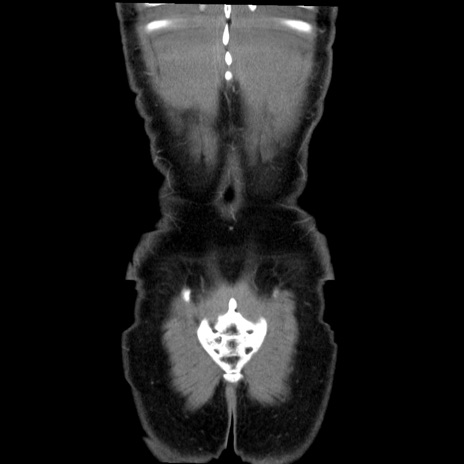

横断像